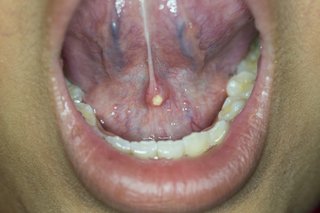

Most stones appear below your tongue. They are usually in one of the glands that supply saliva to your mouth. You cannot always see them.

Salivary gland stones are white and hard.

The inside of a person's mouth showing their lower teeth and part of their bottom lip. There is a small, white salivary gland stone under their tongue.

They vary in size, but can be as big as a pea.